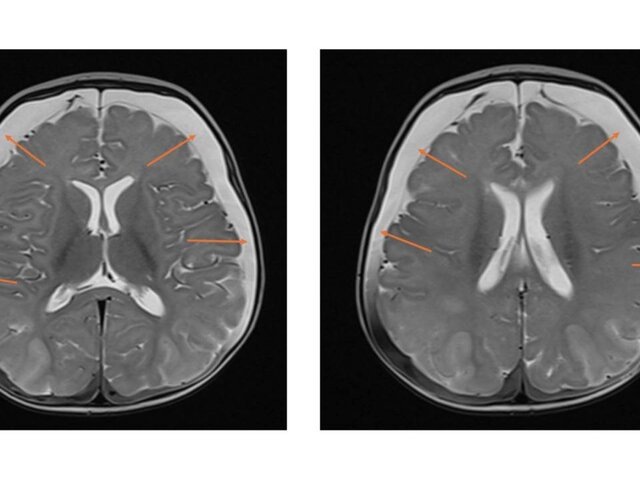

Результаты МРТ показали следы перенесенных кровоизлияний и серьезное нарушение кровоснабжения мозга. Был поставлен диагноз – ННН-синдром, при котором организм не способен перерабатывать белок, что приводит к отравлению мозга аммиаком.